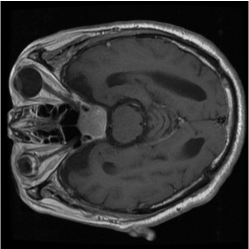

Numerous coreset selection works (Huang et al., 2023; Loshchilov and Hutter, 2015; Marion et al., 2023; Park et al., 2024; Paul et al., 2022; Xia et al., 2022; Yang et al., 2023a) have explored various criteria for identifying important data samples, including geometry distance (Sener and Savarese, 2017; Welling, 2009), uncertainty (Coleman et al., 2019), loss (Toneva et al., 2018; Paul et al., 2021), decision boundary (Ducoffe and Precioso, 2018; Margatina et al., 2021), and gradient matching (Mirzasoleiman et al., 2020). However, most of these methods have been validated mainly on natural image datasets, such as CIFAR-10, CIFAR-100 (Krizhevsky et al., 2009), and not extensively on medical datasets. The applicability of those methods for medical image datasets are under exploration, given the unique characteristics of medical images. Compared to natural image datasets, the intra-class variation and inter-class similarity of medical image datasets (Song et al., 2015) pose specific challenges to coreset selection. On the one hand, in medical imaging, samples within the same category can exhibit significant differences, making it difficult to capture consistent features for each class. This variation largely comes from the diversity in disease manifestation across patients and discrepancies in imaging conditions. On the other hand, the challenge of inter-class similarity arises when images representing different diseases exhibit similar visual characteristics. fig. 6 provides a more straightforward demonstration of this characteristic. These factors contribute to the complexity of medical image analysis and underscore the need for sophisticated coreset selection methods that can effectively address these challenges.

Despite the substantial progress, integrating deep learning into medical imaging is fraught with challenges (Ker et al., 2017). The effectiveness of DL in this context is largely dependent on the availability of large, well-annotated datasets tailored for specific tasks and reliant on advances in high-performance computing. The necessity for vast complex datasets introduces complications such as inconsistencies in data quality, arising from variations in imaging equipment and protocols. Moreover, the extensive volume of medical data demands significant computational resources, posing logistical challenges for efficient processing (Zhou et al., 2021). Additionally, the inherent heterogeneity of medical images, characterized by a multimodal probability distribution, complicates the model training process by requiring algorithms capable of handling diverse visual features and patterns within the data. Another issue is the inter-class similarity and intra-class variation, as depicted in fig. 6, where different diseases may appear similar, and the same disease may present differently across patients.